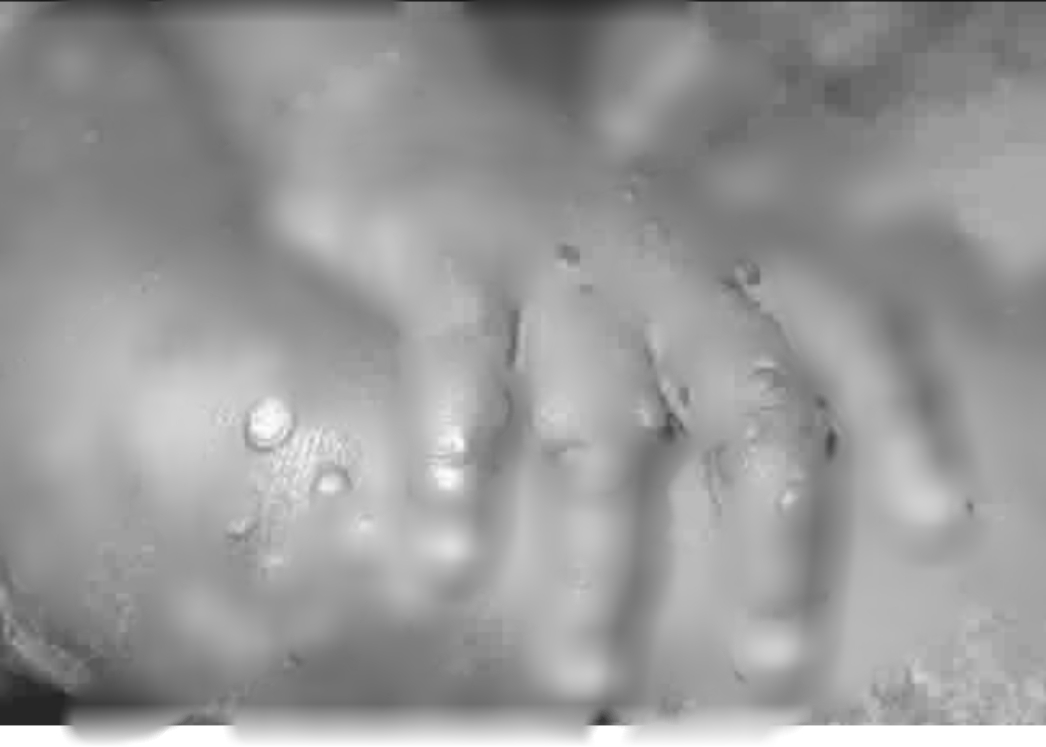

Symptoms of monkeypox include: severe headache, fever, back pains, etc. Most worrisome of all the signs are rashes bigger than those caused by chicken pox.